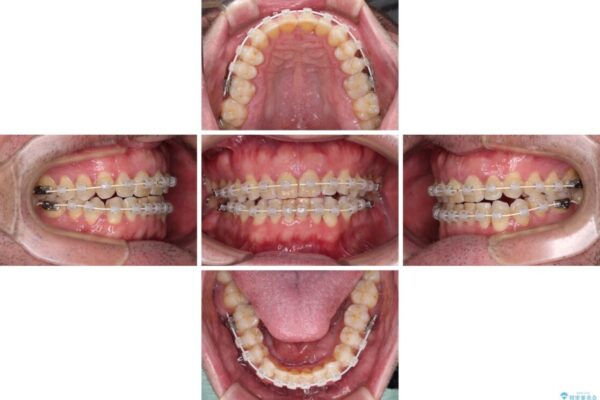

治療途中

• 前歯でものを噛みきりたい 目立たない装置でのワイヤー矯正 治療途中画像